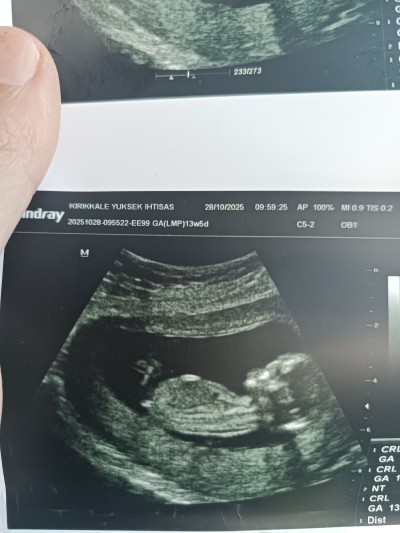

cinsiyet tahmini olan varmi

Gebelik haftası 13+4

Çıkıntı var gibi duruyor kıza benzettim rabbim sağlıklı bir şekilde kucağınıza almayı nasip etsin inşallah 🥰

Çıkıntı olunca erkek oluyor 3 çizgi olunca kız oluyor, ve bebek kız

Nub çıkıntısı kıza benziyor